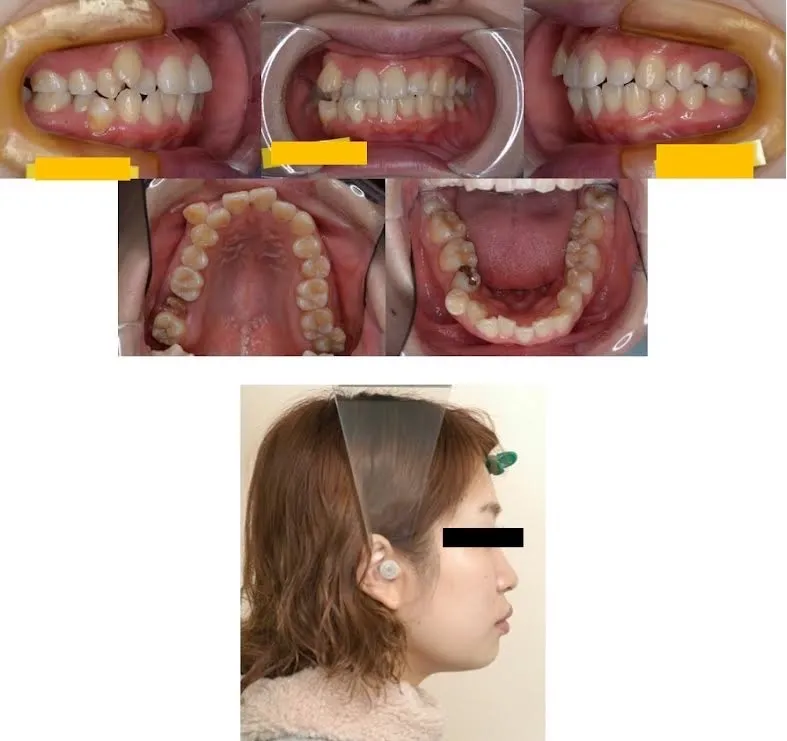

施術前

施術中